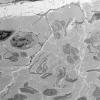

PERIPHERAL NEUROPATHY

4 AXONAL DEGENERATION

3 Electron Microscopy (6)